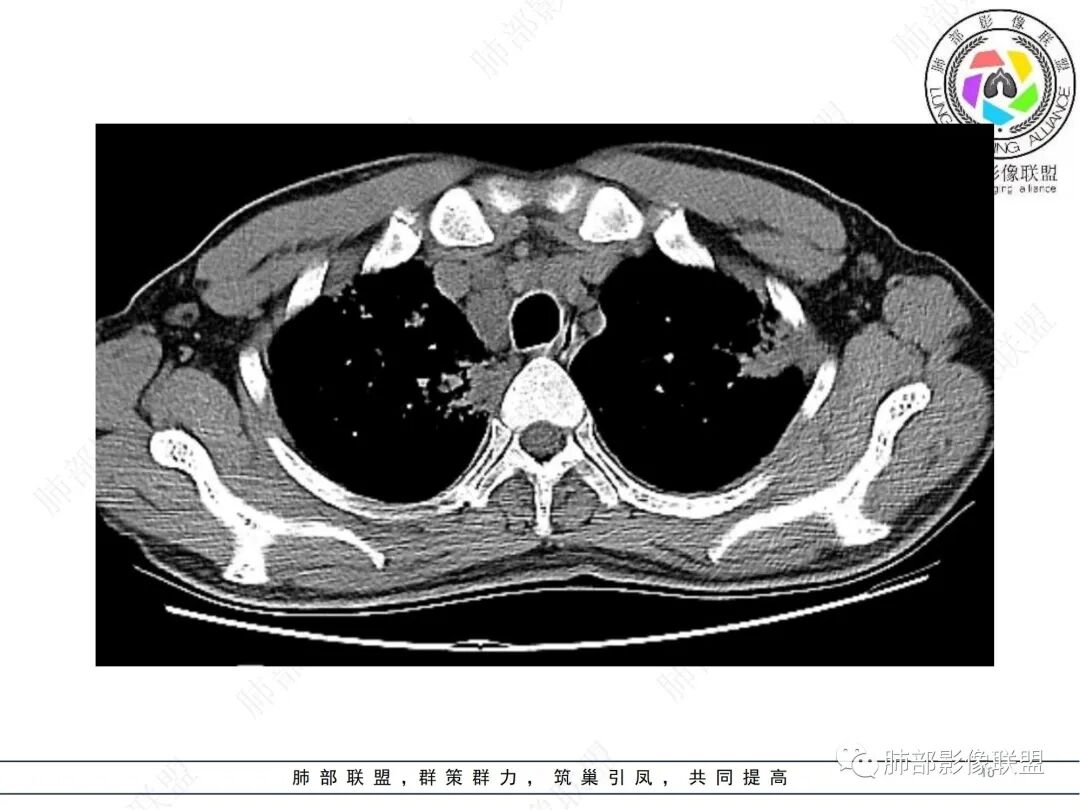

男,咳嗽咳痰一周,肿标阴性,双肺多发胸膜下为主斑片结节状影,小叶中心结节,轻度强化,双侧锁骨上纵隔双肺门多发肿大淋巴结,考虑结节病,鉴别淋巴瘤结核

中年男性,急性呼吸道症状;肿标正常。肺部CT:两肺支气管血管束分布、胸膜下分布的星系状粟粒结节,双侧肺门对称性结节,纵膈多发结节,无明显融合,边界清楚,密度均匀,增强轻中度均匀强化,无坏死,考虑结节病,鉴别结核。

双肺多发实变,边缘见平直及u型凹,实变周围多发弥漫粟粒结节呈星系征样改变,轻度强化,实变内可见血管影,双肺门及纵隔淋巴结肿大,肿大淋巴结无融合,年轻患者,无TB中毒征状,首选结节病

2.影像特点:双肺多发实变,结节状、斑片状、斑点状影,成簇分布趋势,密度不均(部分密度较高),多数位于胸膜下或支气管血管束周围,与支气管关系密切,部分气管壁钙化,部分实变影周围多发弥漫粟粒结节呈星系征样改变,呈轻度渐进性强化,未见空洞。双肺门及纵隔淋巴结肿大,并显示融合,其中后纵隔肿大淋巴结间可见血管影穿行。右侧胸膜增厚伴少量胸腔积液。